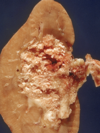

How does a Renal Cell tumor present grossly?

• Hemorrhage and Necrosis are common - hemorrhage most likely related to highly vascularized tissue arising from VHF mutations leading to HIF-1alpha and ultimately VEGF release

What type of cancer is seen here?

Renal Clear Cell Carcinoma

• solitary, well defined, polar

• YELLOW, cysts , necrosis, HEMORRHAGE